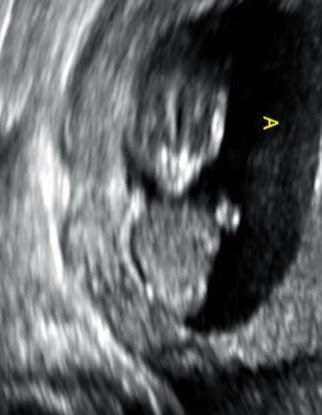

Agree with everyone else. I'm sure it's there, but I see no nub. It's just too early to distinguish anyway. If you absolutely can't wait until the anatomy scan, there are places you can get an elective ultrasound sooner.

I always thought when people said "nub theory" it had something to do with the arm/leg nubs lol! I also checked my ultrasounds and I'm with @KLake42, they're aliens, both of them.